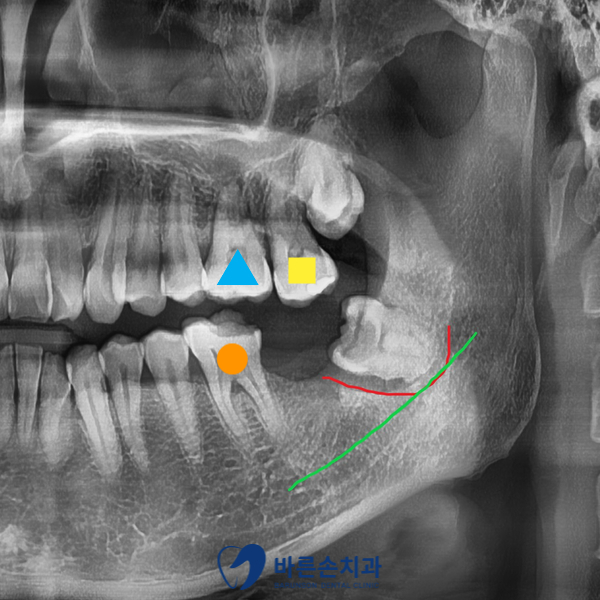

환자분의 파노라마 판독 결과 및 치료계획을 설명드리자면!

빨간 선 : 염증으로 인해 뼈가 내려가 있는 상태 ▷ 발치

▲ : 금이 간 치아 ▷ 발치

■ : 정출 치아 ▷ 신경치료, 크라운

● : 파절 치아 ▷ 신경치료, 크라운

녹색 선 : 신경